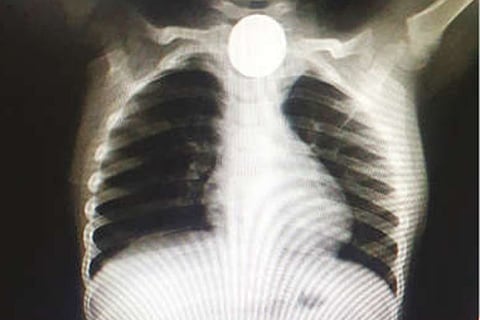

Doctors attached to Tiruvannamalai Government Medical College Hospital successfully removed a Rs 1 coin stuck in the throat of a 2-year-old.

According to ENT surgeons Elanchezhian and Kamalakannan and Dr Balamurugan the anesthetist, the coin was swallowed by Mithun (2) son of Loganathan (24) a daily wage earner in the town.

As the parents were unable to remove the coin themselves, they took the boy first to a private hospital from where he was referred to the Tiruvannamalai GMCH. Dr Elanchezhian said the coin was removed in 20 minutes using an endoscope and that the boy was fine.